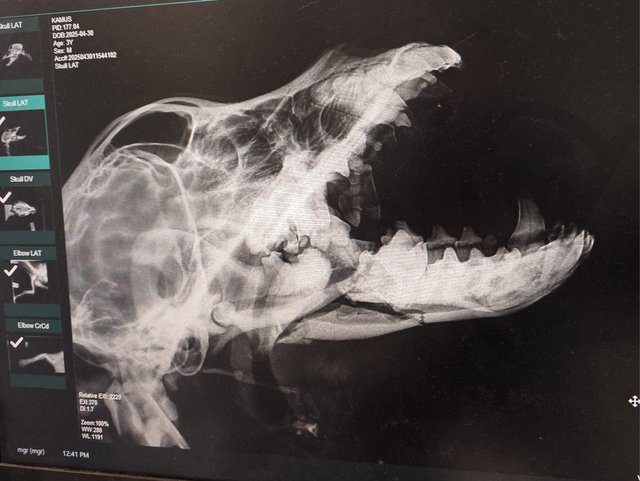

Röntgenbilder zeigten das Ausmaß der Zerstörung des Unterkiefers und den Bruch eines Beines.

Dieser Hund muss grausame Schmerzen haben, Zähne sind aus der Verankerung gerissen und sein Gesichtsschädel ist nicht mehr symmetrisch. Ein großes Stück des Unterkiefers ist komplett abgebrochen.

Es braucht sicher viel Geschick, um das wieder so zusammenzusetzen, dass der Hund später problemlos fressen kann.